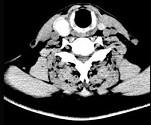

问题 男,43岁,因右颈部扪及一包块来院就诊。如图所示该患者应诊断为()

选项 A.甲状腺腺瘤 B.甲状腺腺癌 C.结节性甲状腺肿 D.甲状腺原发淋巴瘤 E.甲状腺转移瘤

答案 A